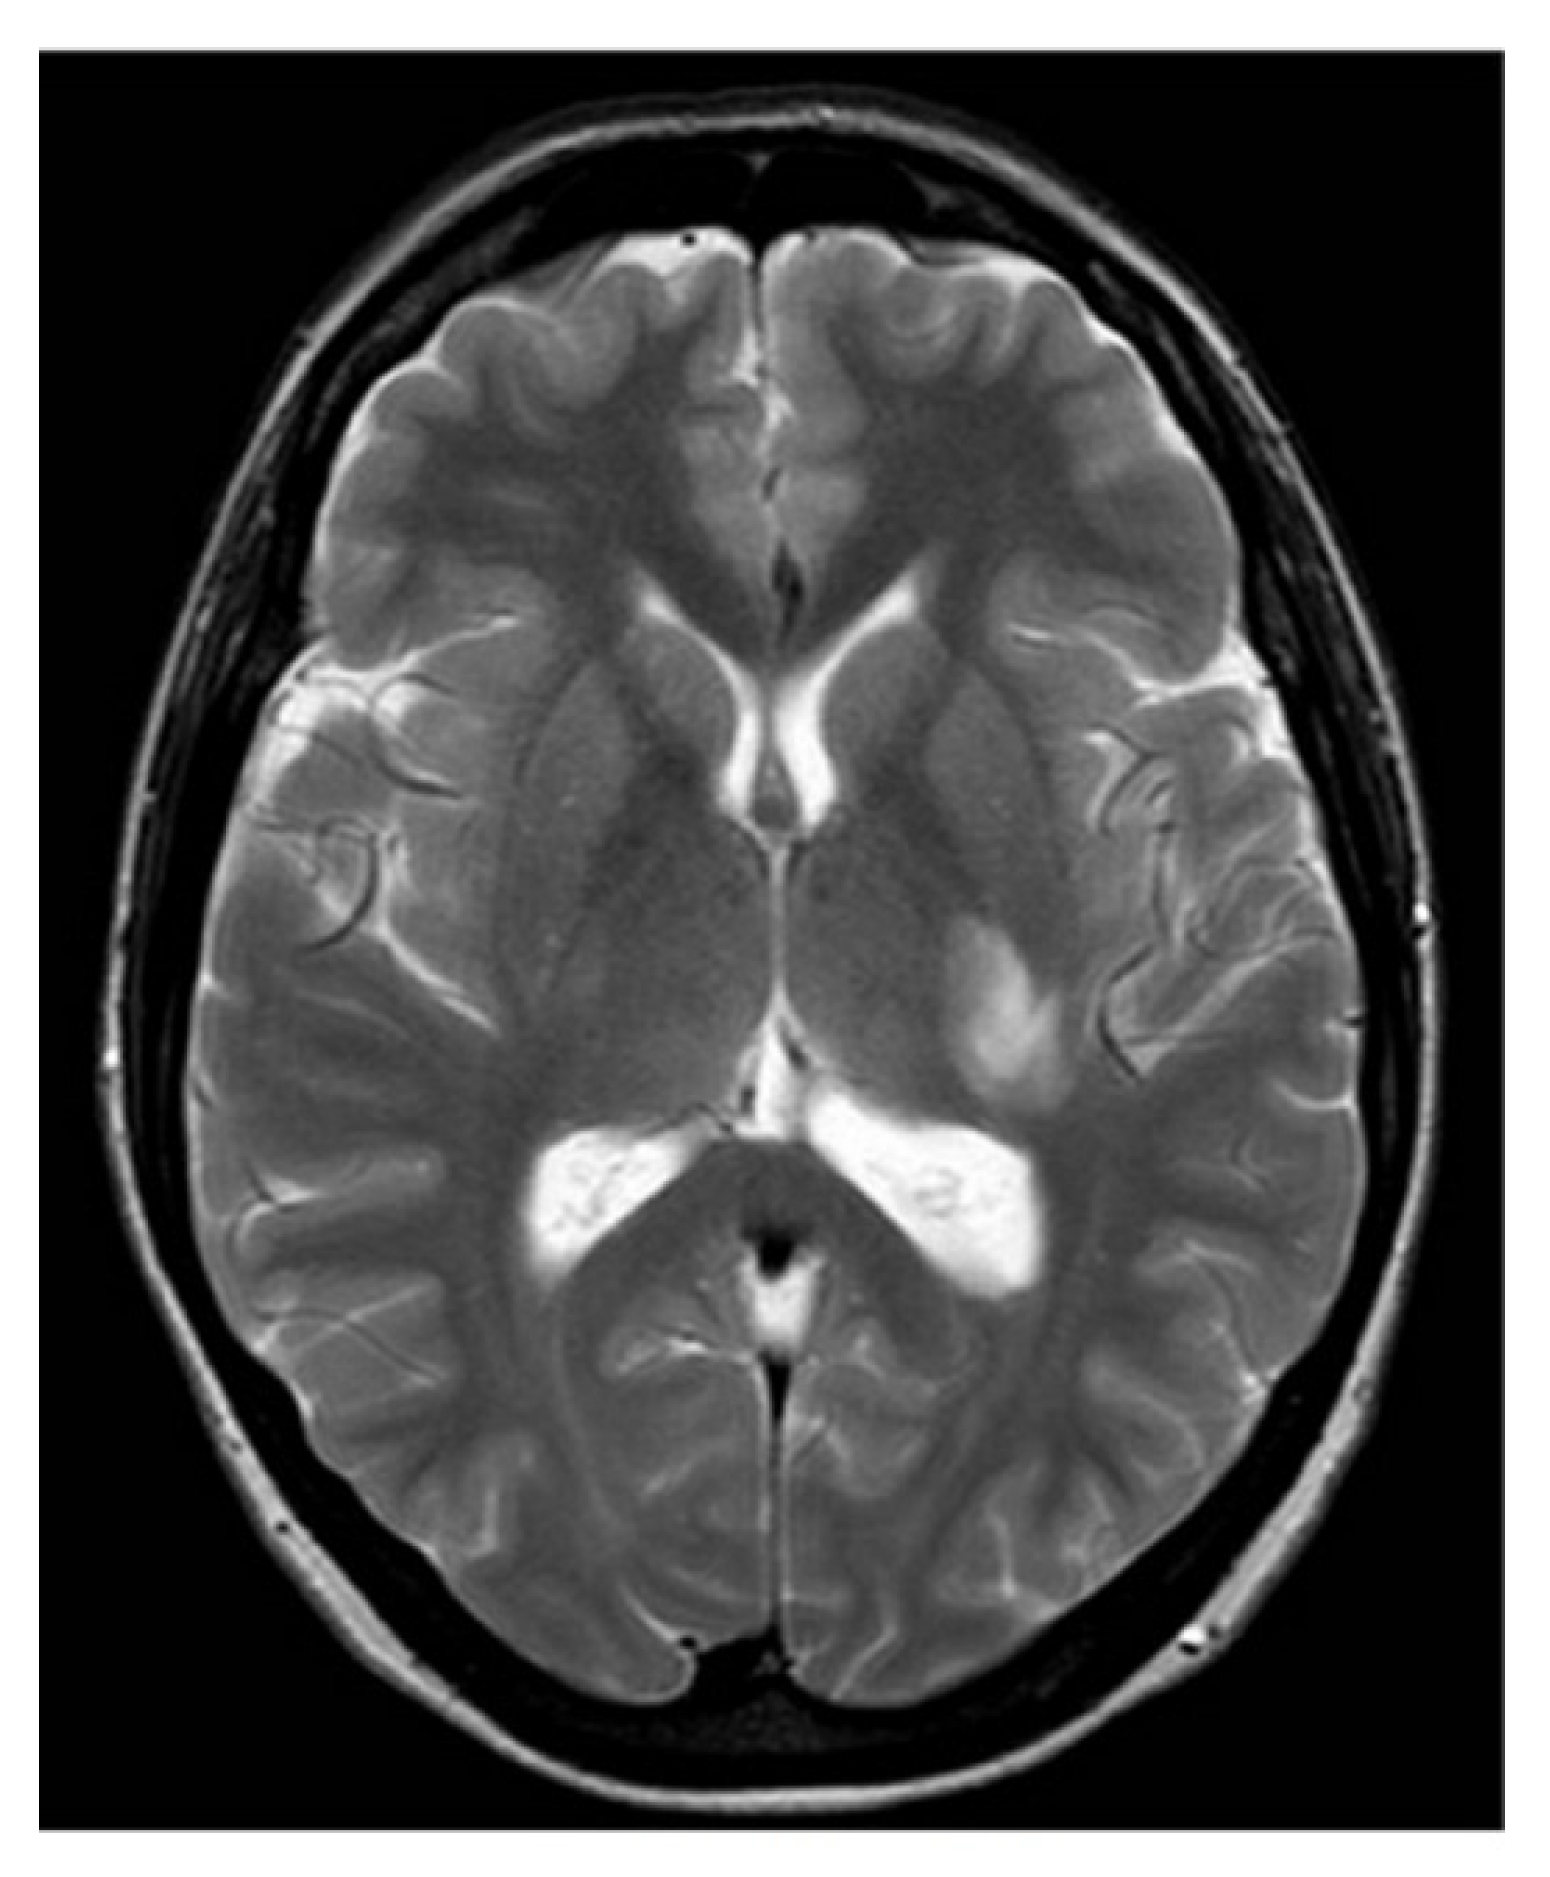

Subsequent magnetic resonance imaging (MRI) of the brain and C-spine revealed an area of hyperintense lesion on T2-weighted imaging involving the posterior limb of the internal capsule, adjacent to the left posterior thalamus with perilesional oedema (Figure 1 and Figure 2). Further hyperintensities were noted in the left frontotemporal region. These lesions demonstrated incomplete ring enhancement with gadolinium and facilitated diffusion restriction, consistent with acute demyelinating lesions. The lesions on the scan did not meet the MAGNIMS criteria for a multiple sclerosis diagnosis.

Figure 1.

T2-weighted axial MRI.